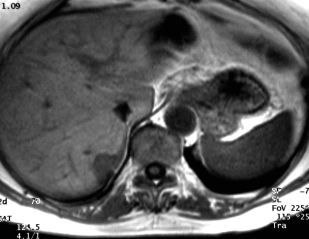

IRM après gadolinium  IRM après gadolinium

La métastase prend le contraste en couronne mais celle-ci est assez régulière et surtout le contraste est moins intense que celui des vaisseaux. L'angiome est difficile à voir car les coupes sont artefactées par les mouvements cardiaques.